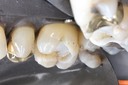

Joe Cha #29 die

Joe Cha #29 finish